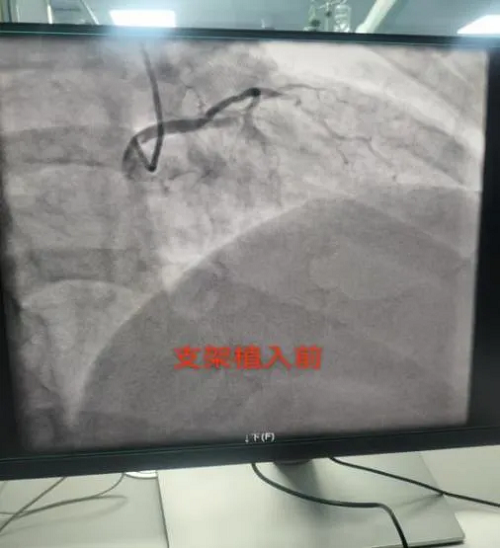

20时15分,冠脉造影提示粗大前降支段完全闭塞,TIMI血流0级,姚远院长及洛浦胸痛中心团队成功为患者开通“罪犯血管”并植入1枚支架,完成血运重建,患者血流恢复正常,患者胸痛胸闷症状明显缓解,生命体征平稳后返回心脏重症监护室。